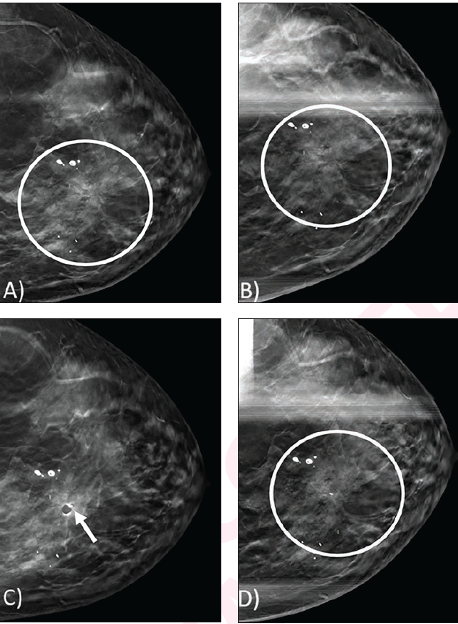

54-year-old woman undergoing breast cancer screening